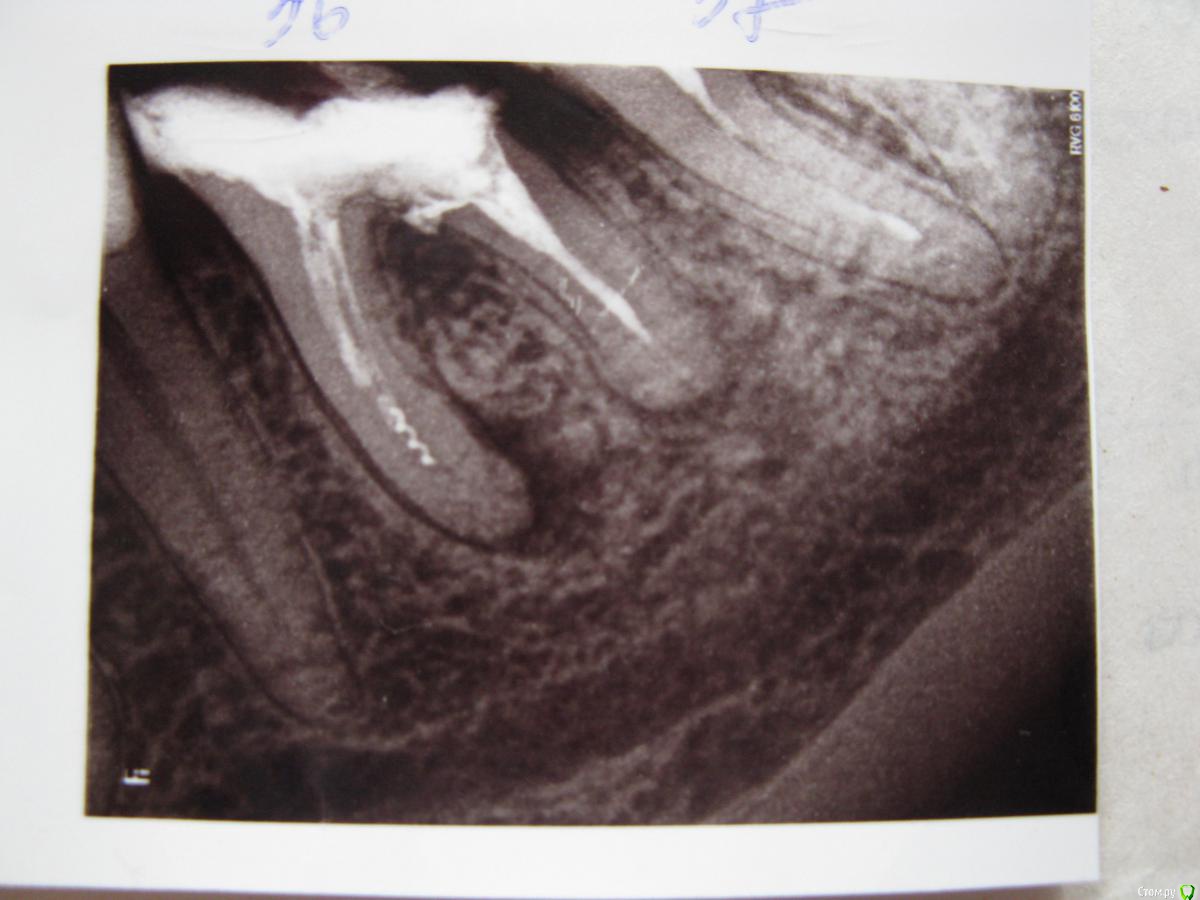

Фотина Опубликовано 18 апреля, 2015 Поделиться Опубликовано 18 апреля, 2015 (изменено) Возможно ли сохранить мои 36-ой и 46-ой зубы?Первый раз зубы лечила много лет назад. В 2014 г. на рентгене обнаружилось хроническое воспаление (кисты?), обломок инструмента и пр. Летом 2014 г. было проведено повторное эндодонтическое лечение: каласепт, пломбирование каналов (где получилось их пройти), депофорез (прицельные снимки после лечения во вложении). Но положительного результата, похоже, добиться не удалось, т.к. в данный момент 36-ой зуб болит при нажатии (46-ой - не беспокоит). Свежий панорамный снимок не показвает улучшений (хотя киста на 46-ом, по-моему, выглядит бледнее, но, ренгенолог сказал, что дело в панорамном снимке) . Что бы Вы могли мне посоветовать (терапевтическое лечение, резекцию, удаление или что иное)? Буду очень благодарна за ответ. Изменено 18 апреля, 2015 пользователем Фотина Ссылка на комментарий